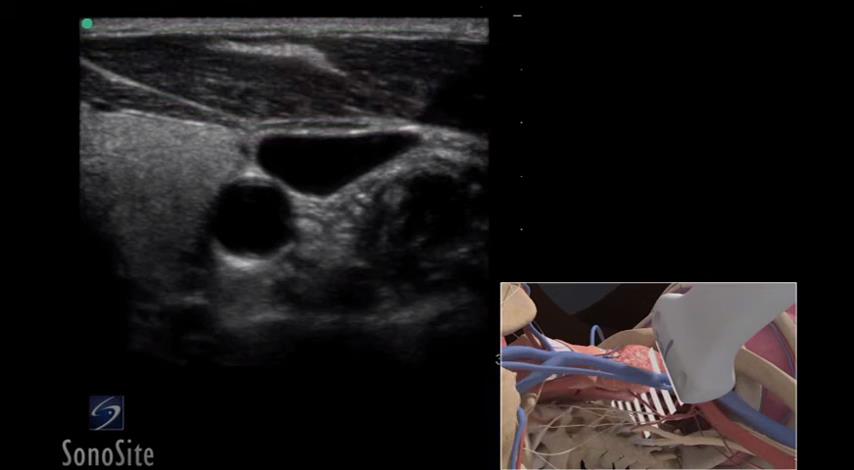

如何操作:超声引导下置入颈内静脉长导管 3D 视频

1、视频截图: